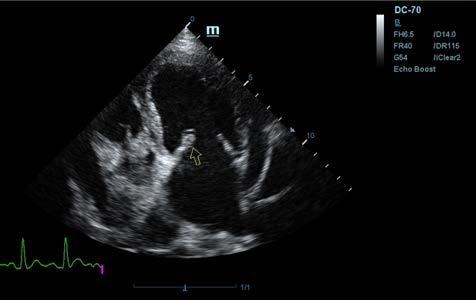

Se realiza ecocardiografía en la cual observamos engrosamiento de la válvula mitral (Fig. 2) y alteración de la estructura de las cámaras cardiacas: ratio atrio izquierdo/aorta 2,25 (Fig. 3), diámetro de ventrículo izquierdo en diástole normalizado (DVIdn) 1,98, patrón de flujo transmitral pseudonormal con velocidad máxima de onda E de 1,7 m/s, tiempo de relajación

isovolumétrica (TRIV) acortado, 30 ms, y regurgitación mitral de hasta 4,6 m/s. En la ecocardiografía se observa también una masa hiperecoica bien definida de hasta 7 x 4,3 cm de diámetro en la base aórtica (Fig. 4) y un acúmulo de derrame pericárdico leve que no permite la pericardiocentesis. Además, se detecta un nódulo hiperecoico redondeado de 1,56 cm de diámetro en la válvula tricúspide (Fig. 5).

Figura 2. Ecocardiografía en corte paraesternal izquierdo eje largo, de 4 cámaras en la que se observa engrosamiento de la válvula mitral (flecha). Figura 3. Ecocardiografía en corte paraesternal derecho eje corto en base de corazón, visualizando ratio atrio izquierdo/aorta aumentado. Figura 4. Ecocardiografía en corte paraesternal izquierdo en base de corazón, en las que se observa la estructura hiperecoica y heterogénea junto a la aorta en un corte de la lesión transversal (A) y otro longitudinal (B). Compatible con neoplasia. A B Figura 5. Ecocardiografía en corte paraesternal izquierdo eje largo, optimizada para válvula tricúspide en la que se observa estructura hiperecoica.

La ecocardiografía es el método de elección para confirmar el diagnóstico de EDVM y estimar la severidad de la regurgitación mitral. Los hallazgos ecocardiográficos incluyen el engrosamiento y/o prolapso de las hojas mitrales junto con la identificación de la regurgitación mediante Doppler. Como se comprobó en el estudio post mortem en nuestro caso, a menudo se observan alteraciones en la válvula tricúspide, pero suelen ser menos marcadas que las de la válvula mitral.2 La ecocardiografía permite adquirir dimensiones del AI en relación con la aorta, o valoración del diámetro del VI en diástole y sístole, muy útiles para estimar el grado de remodelación (agrandamiento) cardíaco.2